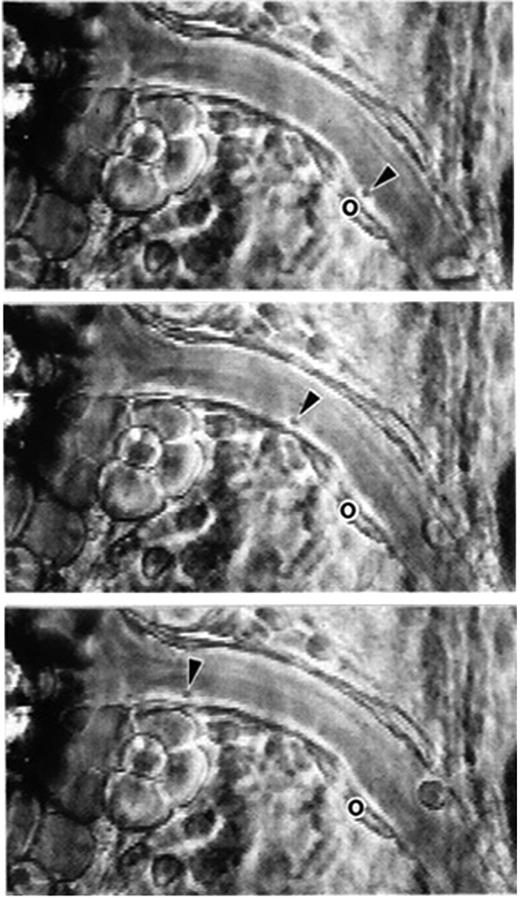

Following vascular injury, the rapid coalescence of blood platelets into forming thrombi was observed by intravital microscopy in the late 1800s (reviewed in Jackson5 ). The adhesion of platelets to presumably intact but stimulated endothelium was documented only in 1970 by Begent and Born.6 After ADP application to the outside of a venule in a hamster cheek pouch preparation, platelets adhered and small unstable thrombi formed. Single platelet rolling on a stimulated venule of the mesentery was detected relatively recently, likely due to the small size of the platelet.7 This mouse mesentery preparation was actually introduced by the Born laboratory in the 1970s to measure the velocity of leukocyte rolling and quantify leukocyte adhesion under various experimental conditions (Atherton and Born8 ). In their work, the authors postulated the existence of specific adhesive interactions between blood cells and the vessel wall. The unraveling of the major molecular players activating and mediating such adhesive interactions occupied this field for the next 25 years.

Phase-contrast intravital microscopy showing a platelet rolling on a mesenteric venule after stimulation by the calcium ionophore A23187. “o” indicates the location of the platelet at time 0. Arrowheads point toward the rolling platelet at 0 seconds (top), 1.58 seconds (middle), and 2.96 seconds (bottom). A single much larger and more slowly rolling leukocyte is also seen. Bar represents 30 μm. Reproduced with permission from PNAS.7

Intravital microscopy analyses of leukocyte-endothelial interactions have revealed that much smaller blood corpuscles, the platelets, also roll on the vessel wall (Figure 7).7 Similarly to leukocyte rolling, platelet rolling increases upon endothelial activation and is observed mainly in veins. The release of WPB components is crucial in mediating this interaction. Interestingly, the identity of the predominant adhesion molecule from the WPB that mediates platelet rolling depends on shear. In small venules where shear is higher, P-selectin supports a true rolling motion of the platelets. The counterreceptor on the platelets is PSGL-1 or GPIbα100,101 (Figure 8). Platelet interactions with stimulated veins of lower shear are much more prominent and are primarily mediated by VWF.102 A carpet of platelets forms within seconds after WPB secretion. These translocate slowly downstream in a manner similar to observations of in vitro translocation of platelet GPIbα on VWF.103 In the absence of additional stimulation, platelets disengage from the vessel wall in a few minutes and return to circulation. Their release is mediated by cleavage of the VWF by the plasma metalloprotease ADAMTS13 (a disintegrin-like and metalloprotease with thrombospondin type I repeats 13),104 the enzyme that is lacking in thrombotic thrombocytopenic purpura (reviewed in Tsai105 ). In the absence of this enzyme, the VWF polymers associate in long strings spanning many endothelial cells to which platelets adhere like beads on a necklace.104,106 Such strings can coalesce and form thrombi in small vessels, a process normally prevented by ADAMTS13.107